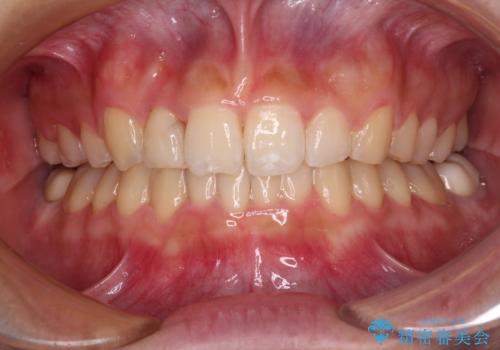

- 強い咬み合わせと前歯のデコボコを気にして来院された患者様です。

下顎前歯が全て隠れてしまうほどの深い咬合で、左右の奥歯は1歯対1歯で咬み合う状態でした。

前方に移動している上顎臼歯を補助装置にて遠心移動させることで1歯対2歯の臼歯咬合を目指し、同時に深い咬合を改善していくこととしました。

このような咬み合わせの場合、治療期間は2年以上がかかることが一般的で、3年程度かかることもありえるケースです。

強く深い咬み合わせにより下顎装置は頻繁に脱離するため、治療期間が長くなりますが、予定通りに終了させることができました。